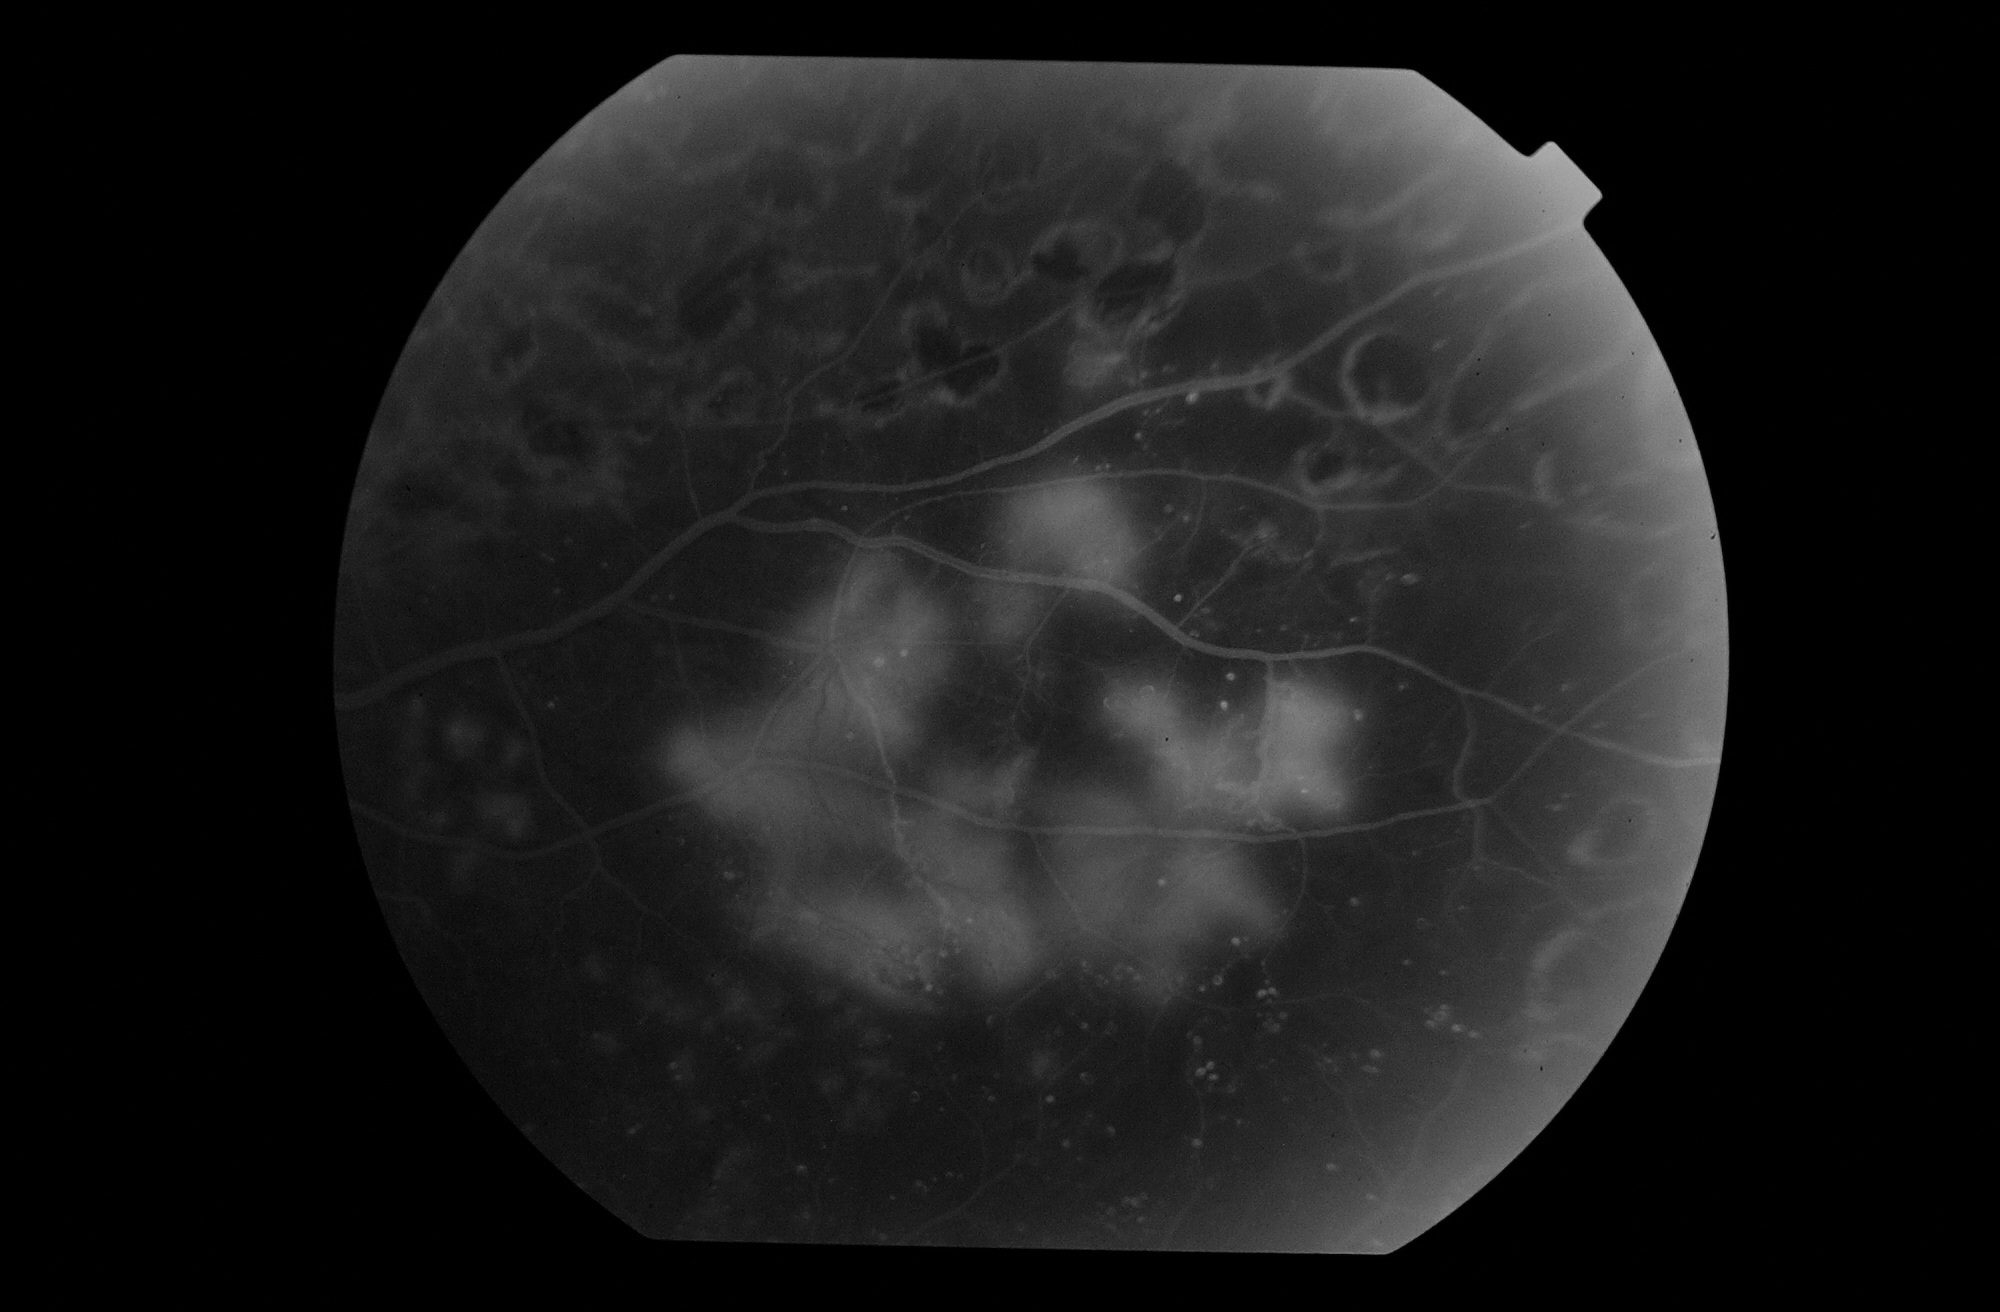

¿Que es la Retinopatía Diabética? La Retinopatía Diabética es un de las principales causas de pérdida de visión en los adultos.

El edema macular diabético es la causa más frecuente de pérdida de visión en la población diabética.